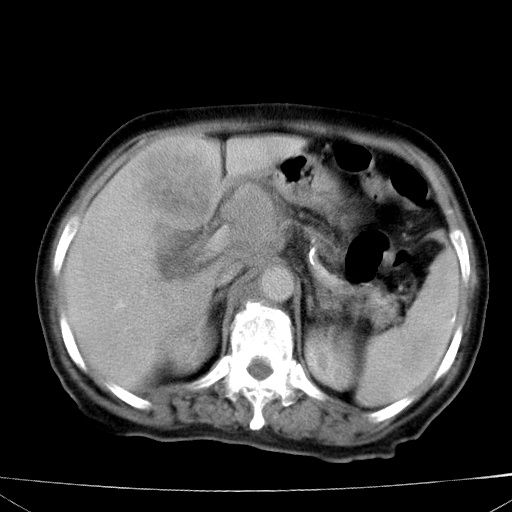

网站人气太旺!昨天的帖子就沉到海底,只好再发贴!ct18338:女 78岁,肝胆病变,已增强,再会诊!原帖链接:http://www.radida.com/bbs/forum.php?mod=viewthread&tid=50032

1)考虑胆囊癌侵犯肝脏并肝门区、腹膜后及右侧膈角后淋巴结转移。2)肝左叶近肝顶部囊肿。3)肝左叶肝内胆管结石。4)左肾近下极囊肿。

1、胆囊癌侵犯肝脏并腹腔及腹膜后淋巴结转移。

2、肝左叶外侧段囊肿。

3,肾囊肿